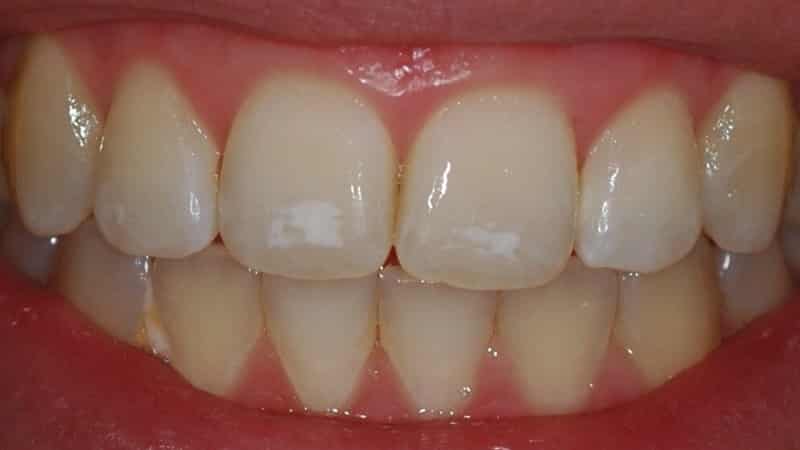

Не все знают, что делать, если на зубах появились белые пятна. Насколько серьезна эта проблема и с чем она может быть связана? Некоторые пятна могут охватывать всю поверхность зуба или даже весь зубной ряд.

Белые пятна на зубах у детей могут иметь желтоватый или коричневый оттенок.